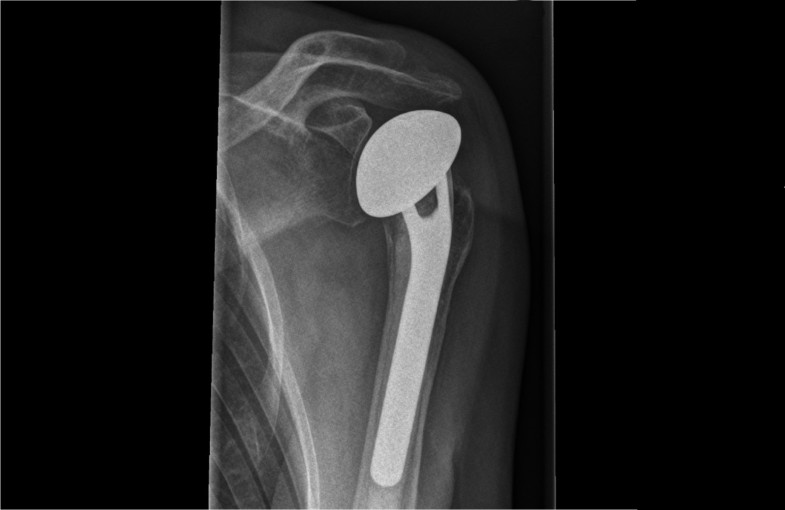

Stable osteosynthesis 07

Stable osteosynthesis 07 picture This picture illustrates Stable osteosynthesis 07.